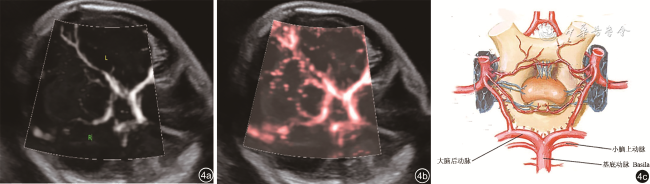

2. 微血流显像检查2例,发育不全侧小脑上动脉均不显示,对侧小脑上动脉可显示(图45)。

图4 正常胎儿小脑上动脉血供超声声像图(图a、b)及小脑上动脉走行模式图(图c),显示小脑上动脉起自基底动脉并与大脑后动脉伴行(图片引自《奈特人体解剖学彩色图谱第6版》)